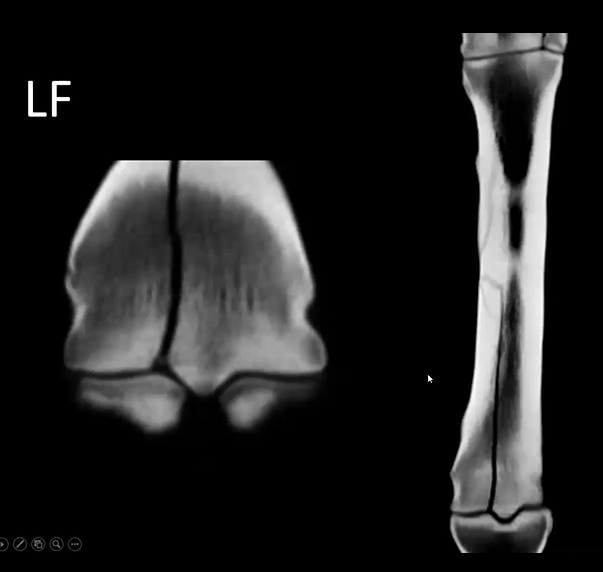

This is an older 7 yo TB racehorse, who received scintigraphy a few years back for a left hind limb lameness. At that time it received a TMT block and was diagnosed with proximal suspensory desmitis. This visit the horse had CT images taken and was diagnosed with Palmar Osteochondral Disease.